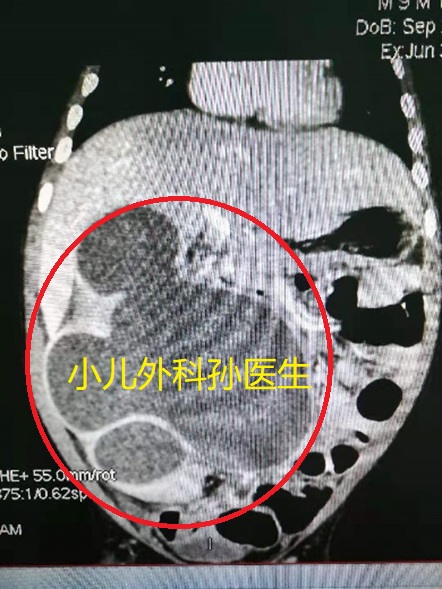

赶紧转来医院,经检查:右肾巨大积水!有多巨大,看图片!

上两图:CT显示的右肾积水(黑色的就是积水,外面薄薄的白色边是肾实质,肾实质有强化显示肾脏还是有点功能的)